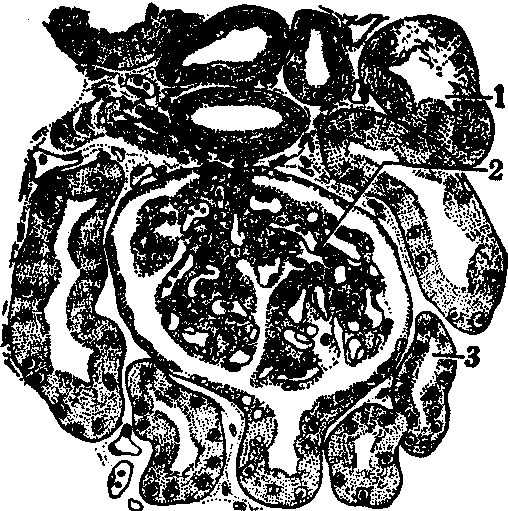

图2 肾皮质切面(光镜)

1.近端小管曲部 2.肾小体 3.远端小管曲部